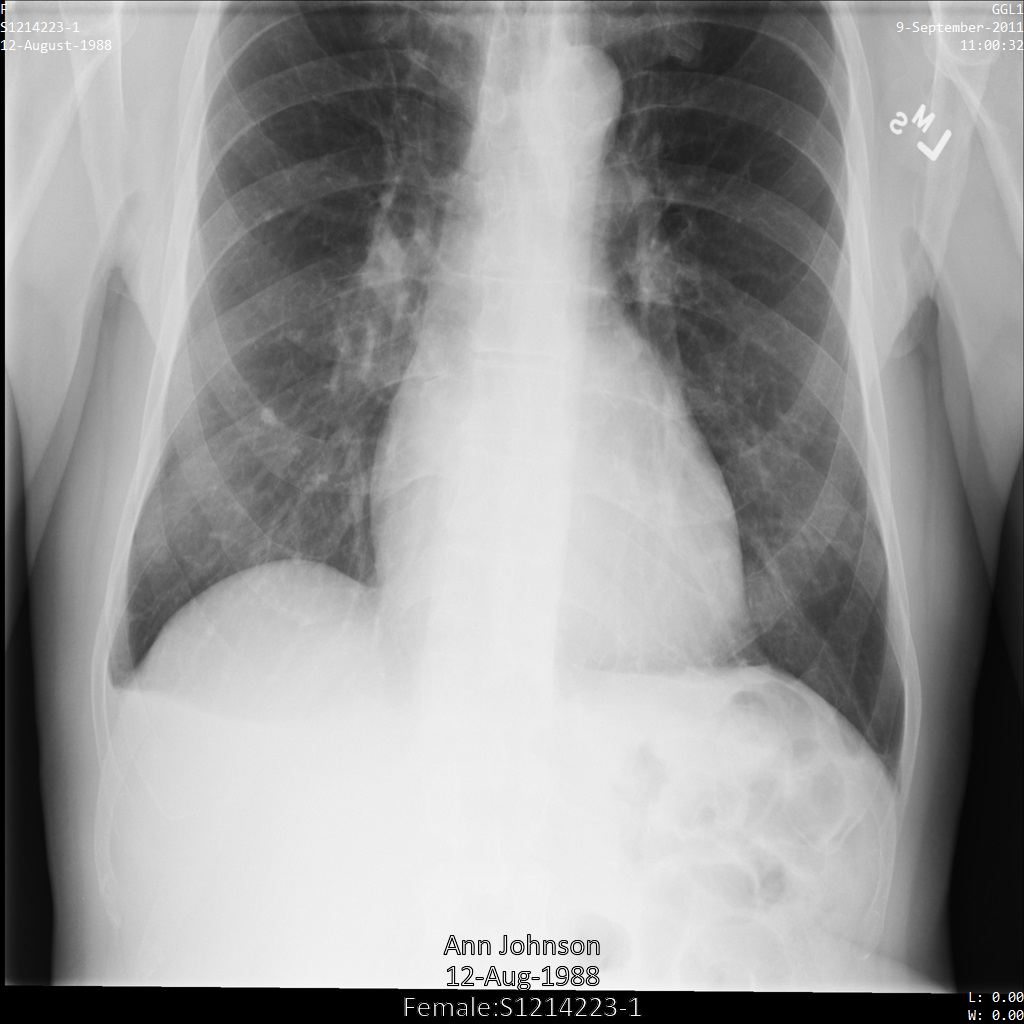

En cada una de las siguientes secciones se proporcionan ejemplos de cómo desidentificar datos DICOM mediante varios métodos. Con cada muestra se proporciona una salida de la imagen anonimizada. En cada ejemplo se usa la siguiente imagen original como entrada:

Puedes comparar la imagen de salida de cada operación de anonimización con la imagen original para ver los efectos de la operación.

Después de enviar la imagen a la API Cloud Healthcare, la imagen aparece de la siguiente manera. Aunque se han ocultado los metadatos que aparecen en las esquinas superiores de la imagen, la información médica protegida (PHI) que aparece en la parte inferior de la imagen no se ha modificado. Para quitar el texto insertado, consulta Ocultar el texto insertado de las imágenes.

REST